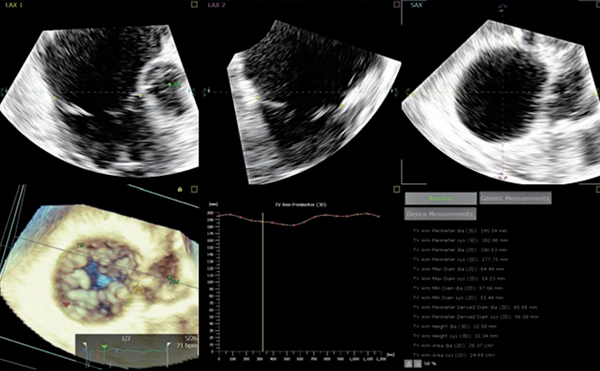

「3D Auto TV」は,エドワーズライフサイエンス社と共同で開発しており,AIが三尖弁の弁輪を認識し,1心周期にわたってトラッキングされ,解析結果が表示される。解析結果画面にはDevice Measurementsボタンも用意されており,SHDデバイス用に必要な計測項目が自動で算出される設計となっている(図4)。

図4 3D Auto TV

1心周期における計測結果のグラフ表示